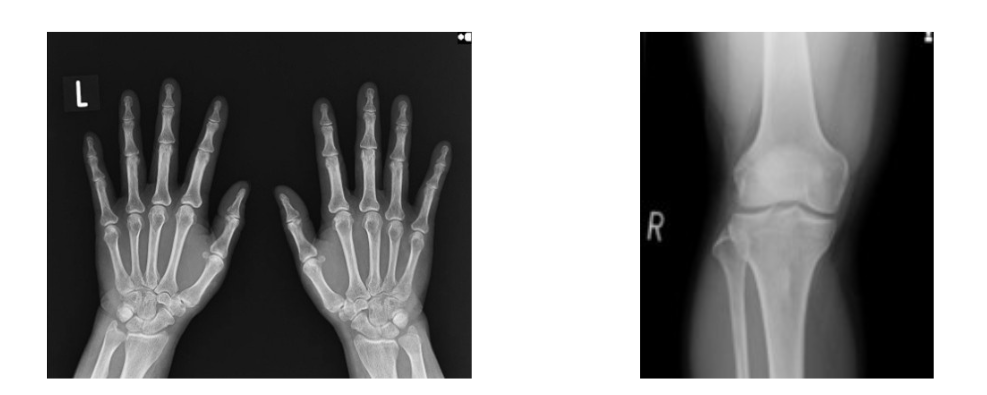

【手】 【膝関節】

骨の撮影では、骨、関節、靭帯の状態や機能、筋肉、脂肪組織の状態を調べます。骨折、脱臼、変形などがわかります。